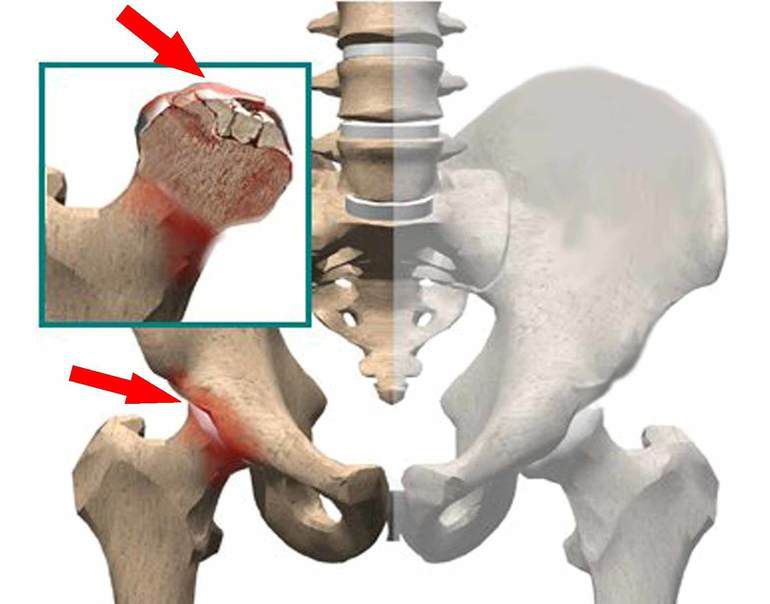

Снижение механической прочности кости приводит к импрессионным микропереломам, что, в свою очередь, уменьшает прочность костной ткани. Из-за нарушения питания и отсутствия адекватной опоры на костные структуры гиалиновый хрящ при асептическом некрозе быстро разрушается и замещается фиброзной тканью.

Дальнейшее течение болезни во многом зависит от локализации пораженного участка. При вовлечении верхненаружной зоны процесс обычно прогрессирует, завершаясь коллапсом головки и быстро развивающимся тяжелым коксартрозом. При некрозе медиальных участков с меньшей нагрузкой в некоторых случаях возможно спонтанное выздоровление.